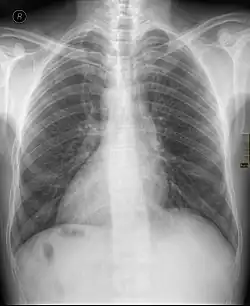

Dextrocardie

La dextrocardie est une malformation de naissance dans laquelle le cœur se trouve dans la moitié droite du thorax, l'hémithorax droit. La pointe du cœur est aussi orientée à droite.